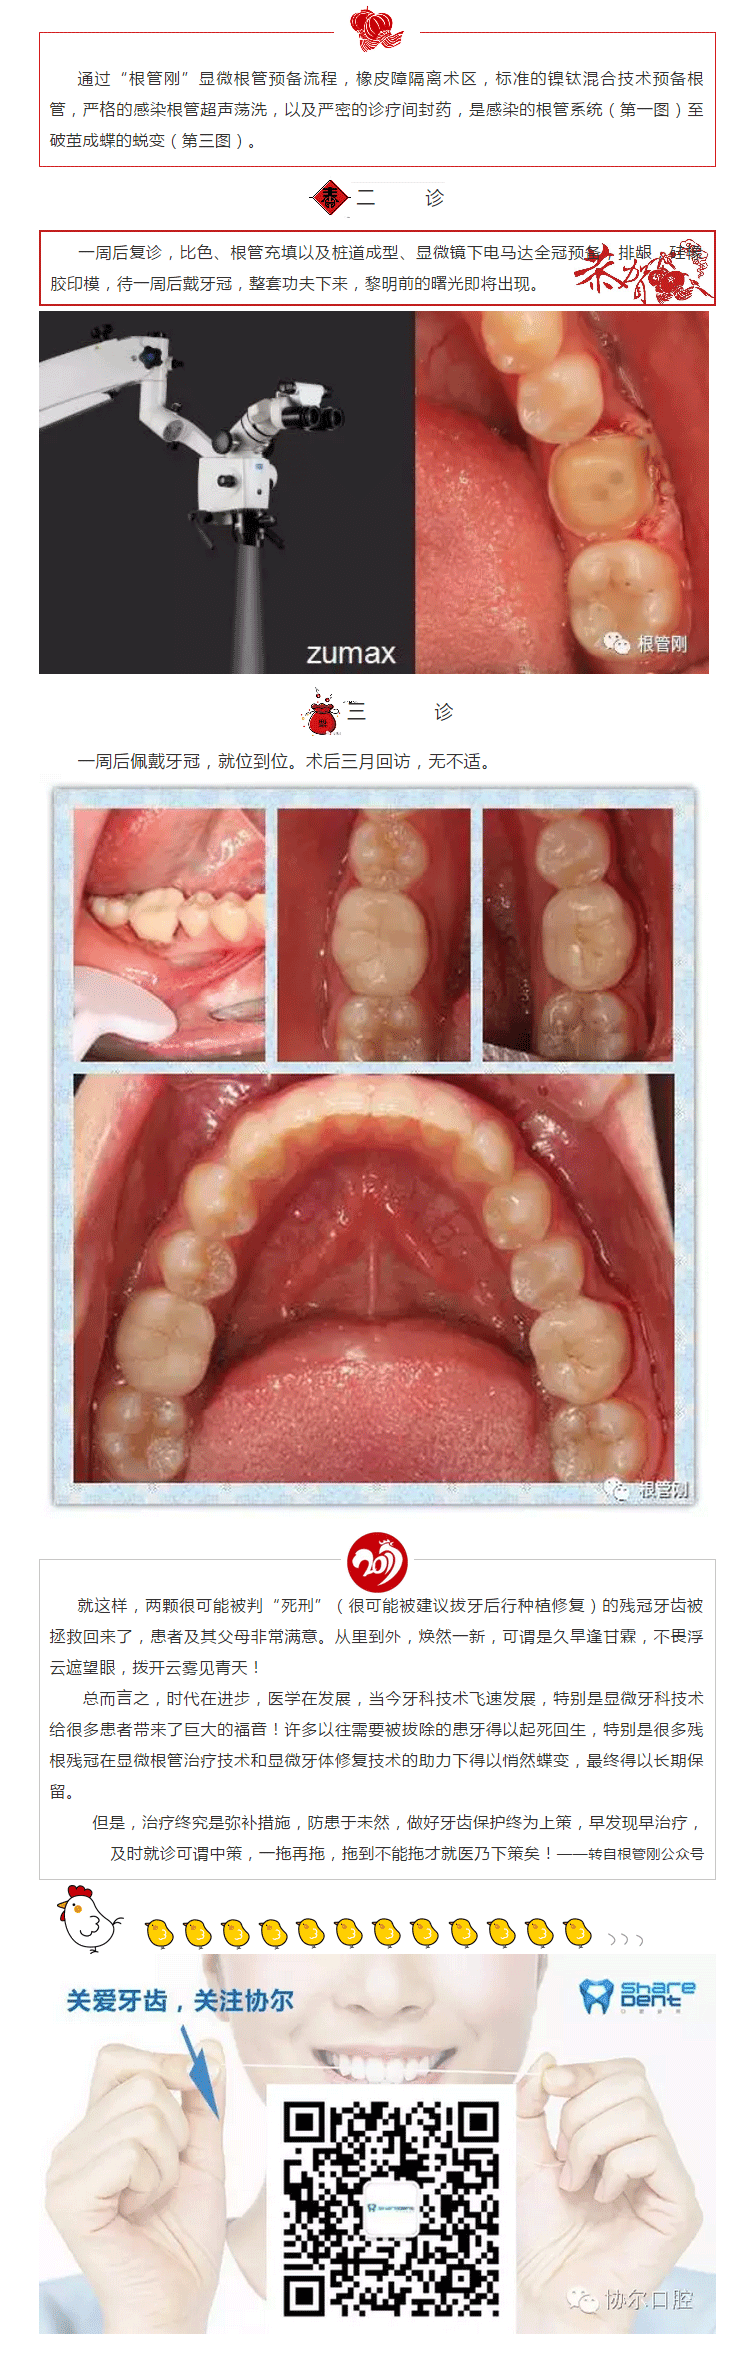

残根残冠最后的“救命稻草”